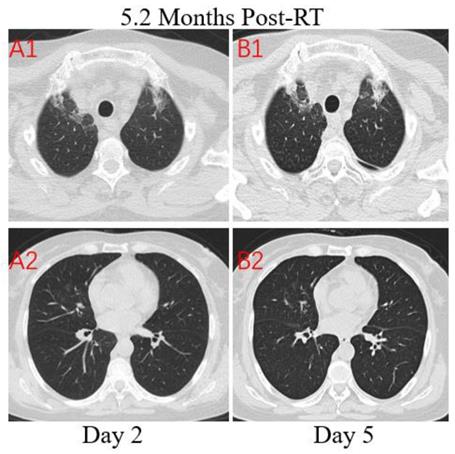

Patient 3: A 64-year-old woman who worked in Beijing was diagnosed with nasopharyngeal carcinoma(T3N2M0) in July 2019 and treated with definitive concurrent chemoradiotherapy followed by adjuvant chemotherapy. She presented to the hospital with a 1-day history of fever (maximum body temperature was 39.5°C), a little cough and headache on February 17, 2020. The patient traveled to Zhuhai and lived in her community where several patients were confirmed COVID-19. At admission, both lungs were clear on auscultation. Laboratory studies showed normal white blood cell, higher neutrophil, and serious lymphopenia. The concentrations of PCT, CRP, D-dimer and NT-BNP increased significantly. The T lymphocyte subsets test showed a sharp drop in CD4+ and CD8+ T cell counts. Results for influenza A and B antigen screening were negative. Chest CT images were obtained on the second day after symptom onset and indicated that there were minimal ground-glass opacities with partially rounded consolidation (Figure 4. A1) in the apexes of both lungs, conforming completely to the irradiated area of low exposure. Multiple ill-defined patchy ground-glass opacities (Figure 4. A2) were observed in the middle lobe of the right lung, considering the possibility of COVID-19 pneumonia. After 3 days of anti-viral therapy with arbidol, antibiotic treatment with sulperazone, and supportive treatment with albumin injection. Follow-up CT demonstrated no obvious changes of lung lesions (Figure 4. B1, B2). However, the patient's symptoms improved significantly. Repeated four times of swab nucleic acid tests for the COVID-19 were negative. Finally, blood culture suggested an Escherichia coli infection. Then the patient was transferred to the Department of Oncology.

Transverse unenhanced thin-section serial CT scans from a 64-year-old female with suspected COVID-19 pneumonia. Chest CT images on the second day after symptom onset found minimal ground-glass opacities with partially rounded consolidation in the apexes of both lungs (A1), and multiple ill-defined patchy ground-glass opacities in the middle lobe of right lung (A2). Follow-up CT on the fifth day demonstrated no obvious change of lung lesions (B1, B2).